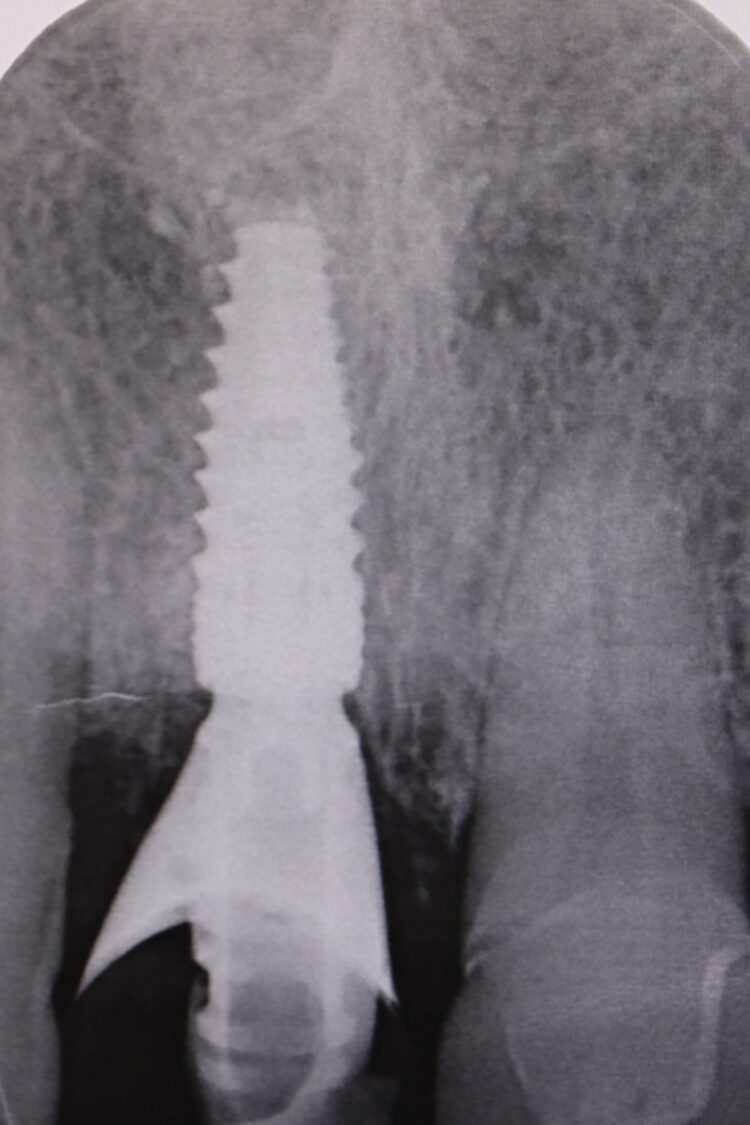

A female patient in her mid-50s was referred due to pain around the gingival margin of the UR1. The tooth had previously been root filled and crowned, and was now unrestorable. External root resorption was confirmed with a periapical radiograph, which showed that the distal bone peak was absent. Located in the aesthetic zone, the missing distal peak meant that the remaining papilla would disappear after the tooth was extracted, and thus needed addressing to avoid the formation of a black triangle.

A post-operative radiograph was taken to confirm that the crestal bone was not compressed and there was no convexity in the area to allow space for the soft tissue graft to expand, proliferate and grow.